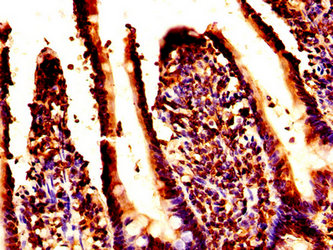

IHC image of CSB-PA010100OA07nacHU diluted at 1:50 and staining in paraffin-embedded human prostate tissue performed on a Leica BondTM system. After dewaxing and hydration, antigen retrieval was mediated by high pressure in a citrate buffer (pH 6.0). Section was blocked with 10% normal goat serum 30min at RT. Then primary antibody (1% BSA) was incubated at 4°C overnight. The primary is detected by a biotinylated secondary antibody and visualized using an HRP conjugated SP system.